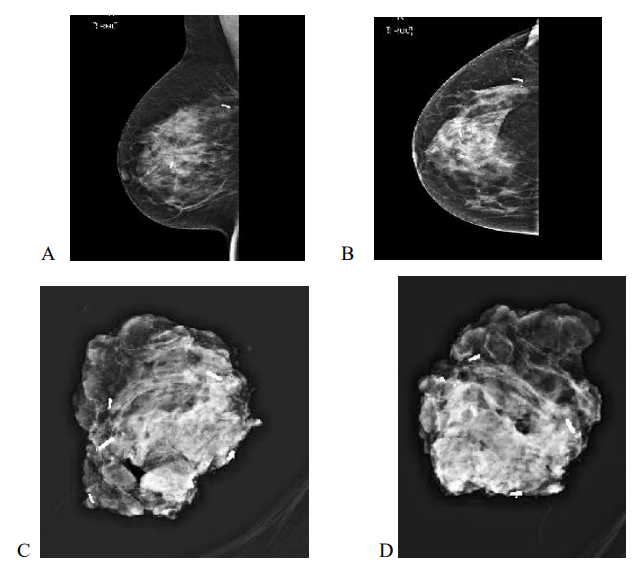

Figure 2: 50yr old with 24 BMI, Bra size 34 B/C with Grade 1 invasive carcinoma measuring 31mm on pre op imaging, post op specimen weighed 58gm, tumerectomy and partial breast reconstruction with lateral intercostal artery perforator flap. Margins clear. Mediolateral and Craniocaudal mammograms showing two RFID tags marking the medial and lateral extent of disease.

Figure 3: 63yr old with 24 BMI, Bra size 36 DD with invasive carcinoma measuring 66 mm on pre op imaging, post op specimen weighed 129gm, tumerectomy and partial breast reconstruction with chest wall perforator flap. Margins clear. Mediolateral (A) and Craniocaudal (B) mammograms showing two RFID tags marking the medial and lateral extent of disease with specimen X rays shows radiologically clear margins (C,D)